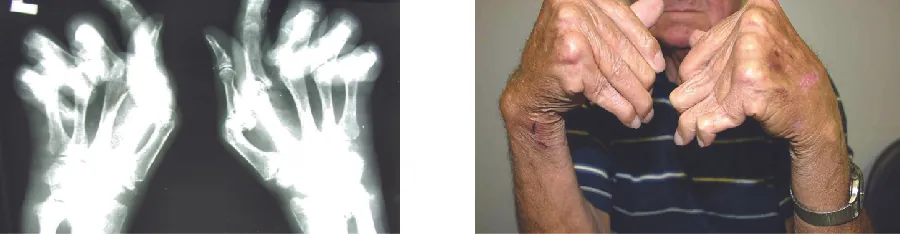

The most common chronic inflammatory joint disease is rheumatoid arthritis (RA) (Figure 19.17) and it is still a major medical challenge because of unsolved questions related to the environmental and genetic causes of the disease. RA involves type III hypersensitivity reactions and the activation of CD4 T cells, resulting in chronic release of the inflammatory cytokines IL-1, IL-6, and tumor necrosis factor-α (TNF-α). The activated CD4 T cells also stimulate the production of rheumatoid factor (RF) antibodies and anticyclic citrullinated peptide antibodies (anti-CCP) that form immune complexes. Increased levels of acute-phase proteins, such as C-reactive protein (CRP), are also produced as part of the inflammatory process and participate in complement fixation with the antibodies on the immune complexes. The formation of immune complexes and reaction to the immune factors cause an inflammatory process in joints, particularly in the hands, feet, and legs. Diagnosis of RA is based on elevated levels of RF, anti-CCP, quantitative CRP, and the erythrocyte sedimentation rate (ESR) (modified Westergren). In addition, radiographs, ultrasound, or magnetic resonance imaging scans can identify joint damage, such as erosions, a loss of bone within the joint, and narrowing of joint space.

X-ray and photo of hands with joints bent at unusual angles.

Figure 19.17 The radiograph (left) and photograph (right) show damage to the hands typical of rheumatoid arthritis. (credit right: modification of work by “handarmdoc”/Flickr)